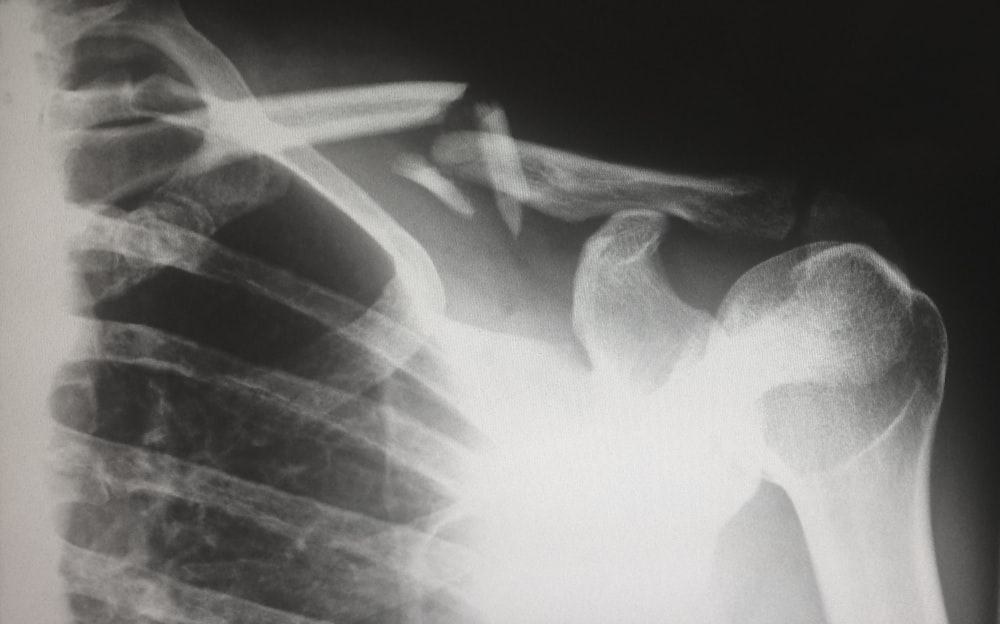

Rotator Cuff Issue

The muscle that provides maximum flexibility to our shoulder is the rotator cuff. It is this particular rotatory movement enabler which makes multiple everyday chores possible for us, and unfortunately the majority of the people end up developing anomalies within it. Something as trivial as brushing your hair properly, or bathing yourself, or even picking up a magazine from behind the table are all tasks dependent on the flexibility and mobility of our rotator cuff. Hence, there is no doubt that it is very important.

The irritations caused within the rotator cuff are usually of 2 types: one in the form of inflammation and the other in the form of tears. If you observe stiffness in your shoulder and find lifting your arm around to have become a painful ordeal, then you have most likely and unfortunately developed either of the two.

Any sign of irritation, inflammation, or compression of the tendons can cause rotator cuff impingement. Everyday exhaustion or even a slight injury to the shoulder can cause it as well. If, along with irritation and inflammation you also feel weakness, then there is a chance that you have developed a rotator cuff tear.